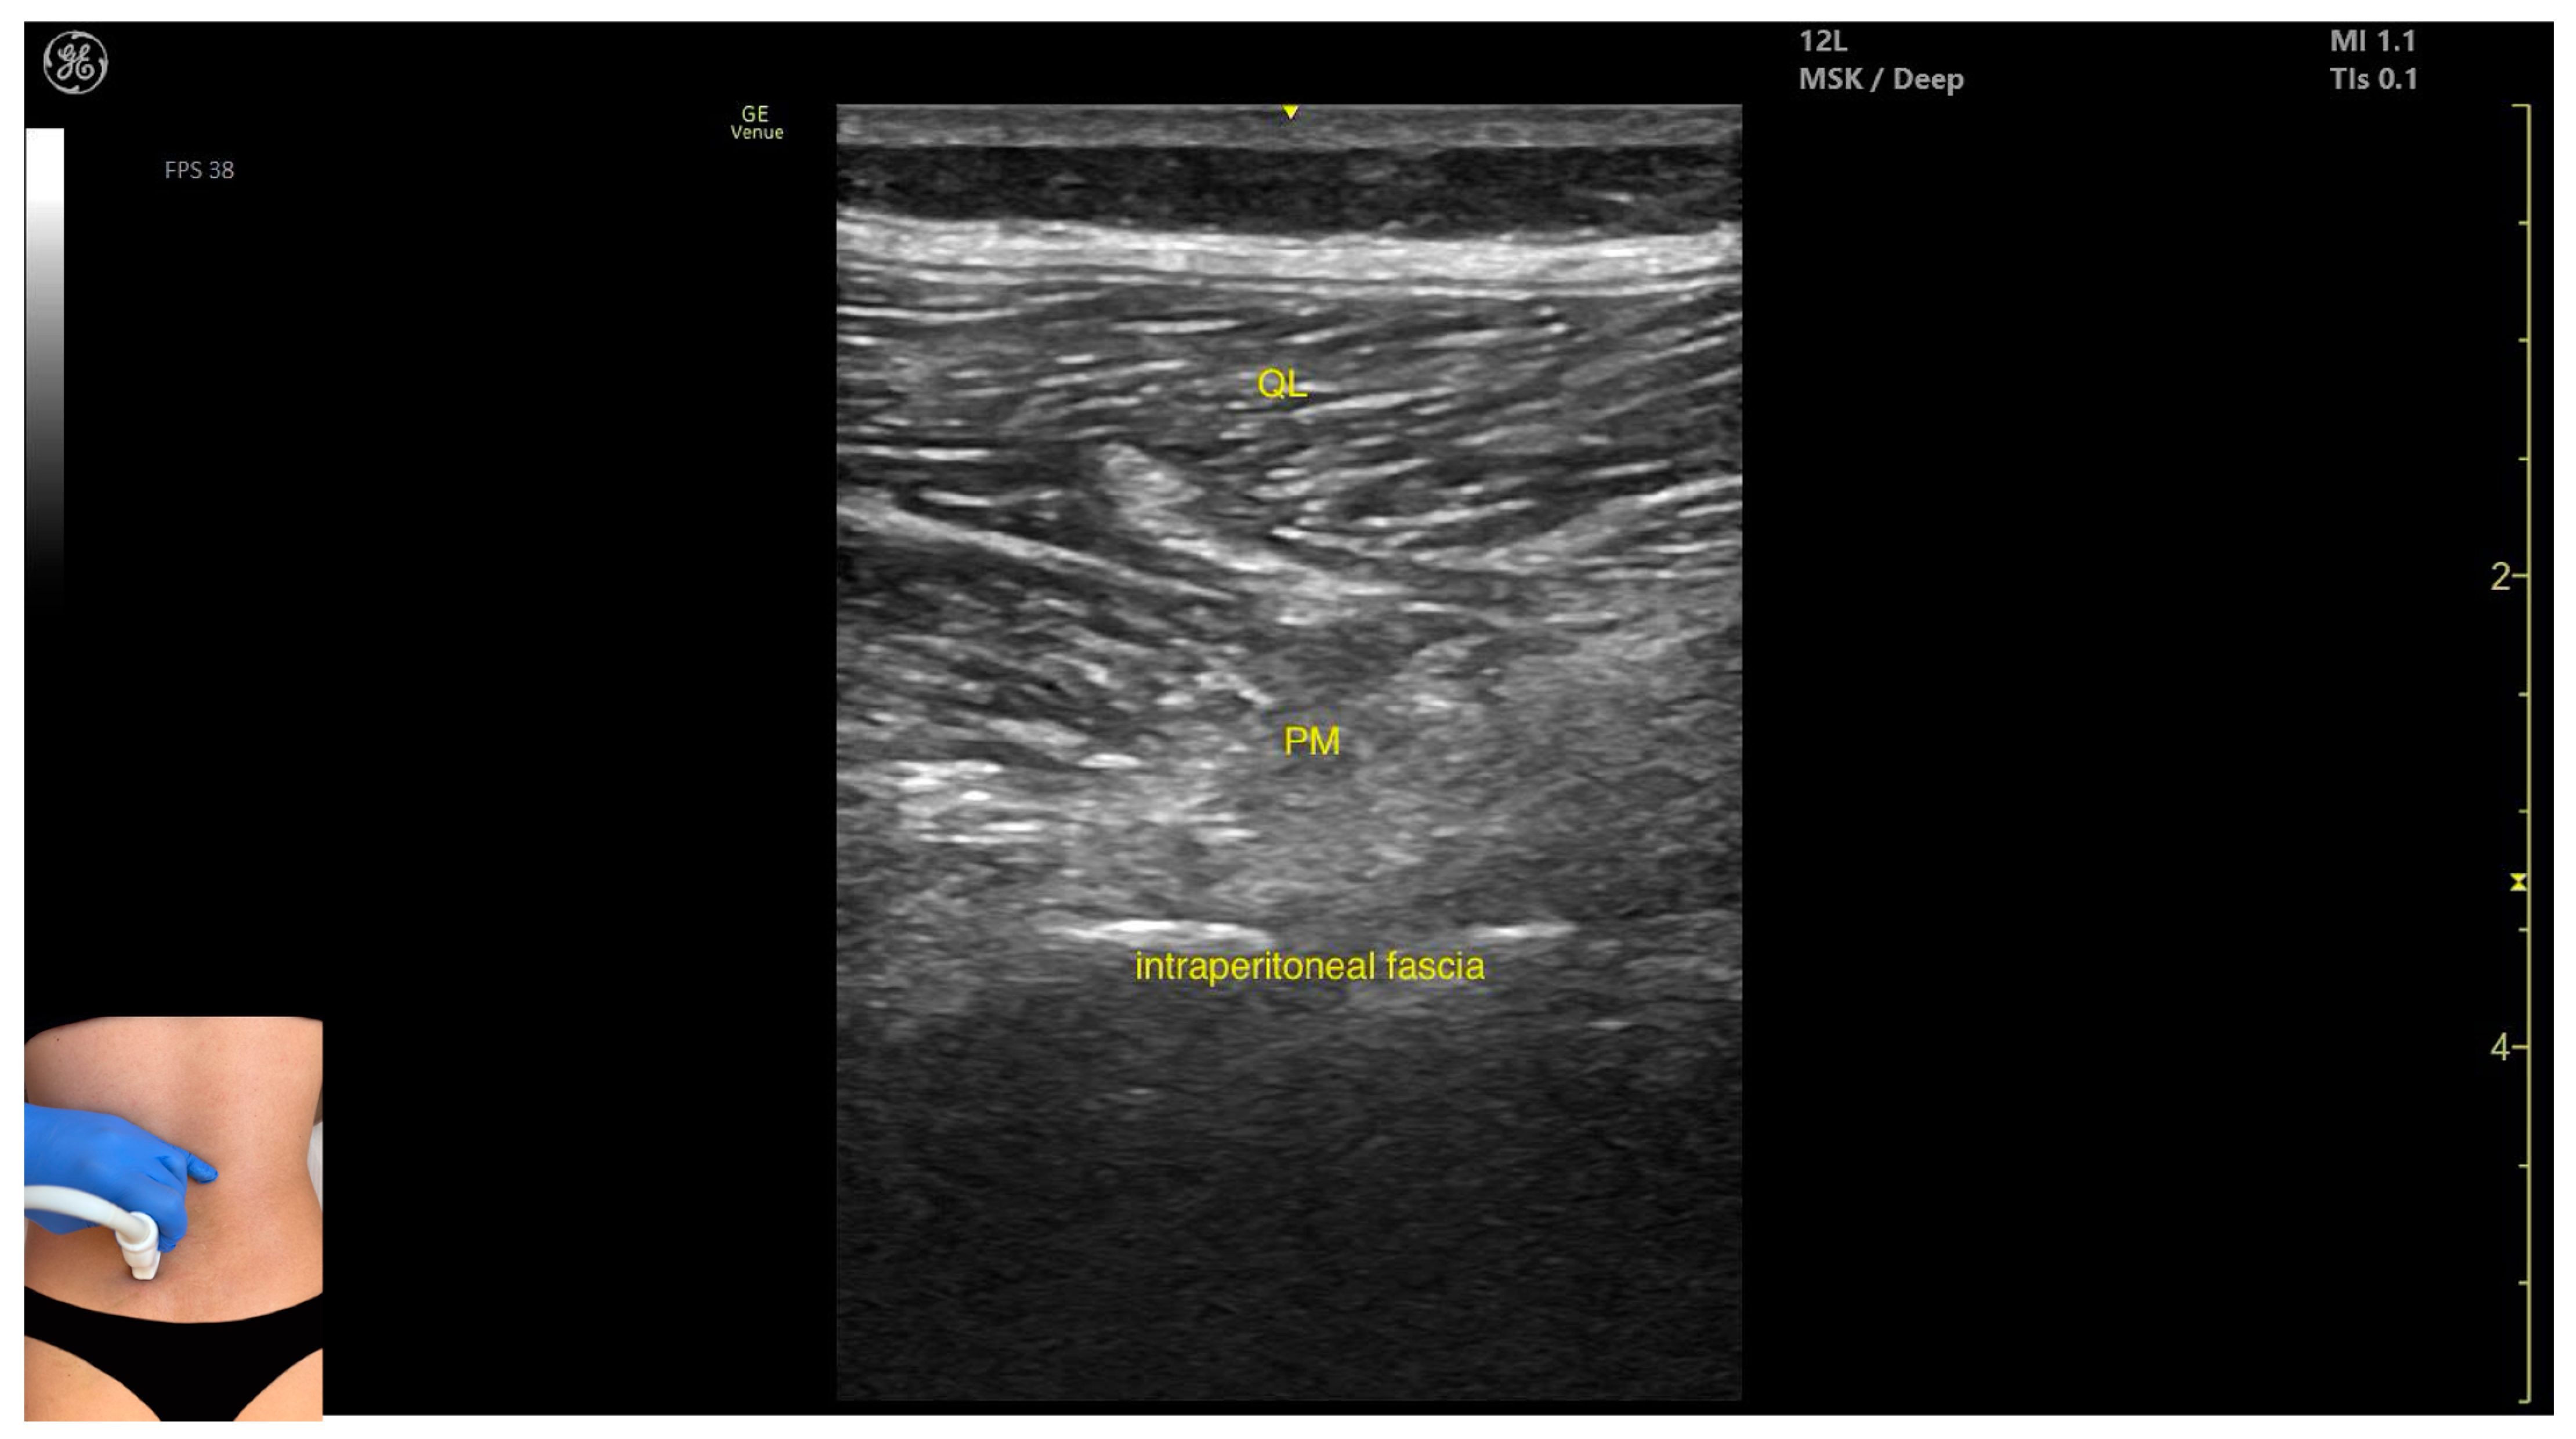

3.3. Psoas Major

3.3.2. Ultrasound Identification

3.3.3. Key Ultrasound Landmarks

- Muscle position: It is the deepest muscle mass at this level.

- External fascia: It presents a pronounced fascia that separates it from the erector spinae and quadratus lumborum, aiding in safe botulinum toxin injection.

- Dynamic evaluation: During dynamic evaluation, when scanning proximo-medially toward the costal arch, its origin is visualized from the T12 to L5 vertebrae.

- Contraction is visible during hip flexion, as well as lumbar spine flexion and lateral inflection maneuvers.

- The psoas major can also be visualized using a longitudinal transducer position, placed superior to the iliac crest and 2 cm lateral to the L4 spinous process. In this view, both the psoas major and the overlying quadratus lumborum are seen superficial to the intraperitoneal space.